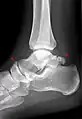

Ankle

Accessory bones at the ankle mainly include:

- Os subtibiale, with a prevalence of approximately 1%.[14] It is a secondary ossification center of the distal tibia that appears during the first year of life, and which in most people fuses with the shaft at approximately 15 years in females and approximately 17 years in males.[14]

- Os subfibulare, with a prevalence of approximately 0.2%.[15]

Os trigonum (further described below) may also be seen on an ankle X-ray.

Os trigonum

The os trigonum or accessory talus represents a failure of fusion of the lateral tubercle of the posterior process of the talus bone. Is estimated to be present in 7–25% of adults.[17] It can be mistaken for an avulsion fracture of lateral tubercle of talus (Shepherd fracture) or a fracture of the Stieda process. In most cases, Os Trigonum will go unnoticed, but with some ankle injuries it can get trapped between the heel and ankle bones which irritates the surrounding structures, leading to Os Trigonum Syndrome.[21]